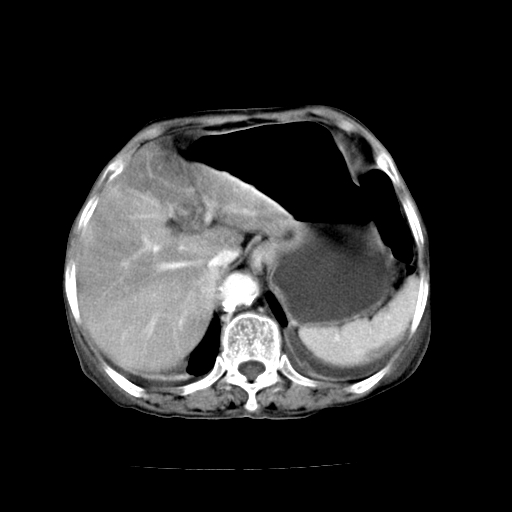

标题: CT19149:女,68岁,腹胀、恶心两周。 [打印本页]

女,68岁,腹胀、恶心两周,先做ct平扫,当时家属不同意强化,6天后家属要求增强扫描。

1、胃窦癌; 2、局灶性脂肪肝。

1、胃窦癌?建议行胃镜!; 2、局灶性脂肪肝。

1.局灶性脂肪肝;2.胃窦癌可能,建议行进一步检查。

1)胃窦壁厚,考虑胃窦癌?建议行胃镜检查。 2)局灶性脂肪肝。

支持考虑1、胃窦癌?建议行胃镜!; 2、局灶性脂肪肝。  3、双侧胸腔积液,胸膜增厚

不均匀脂肪肝,胃腔改变须结合钡餐或胃镜观察